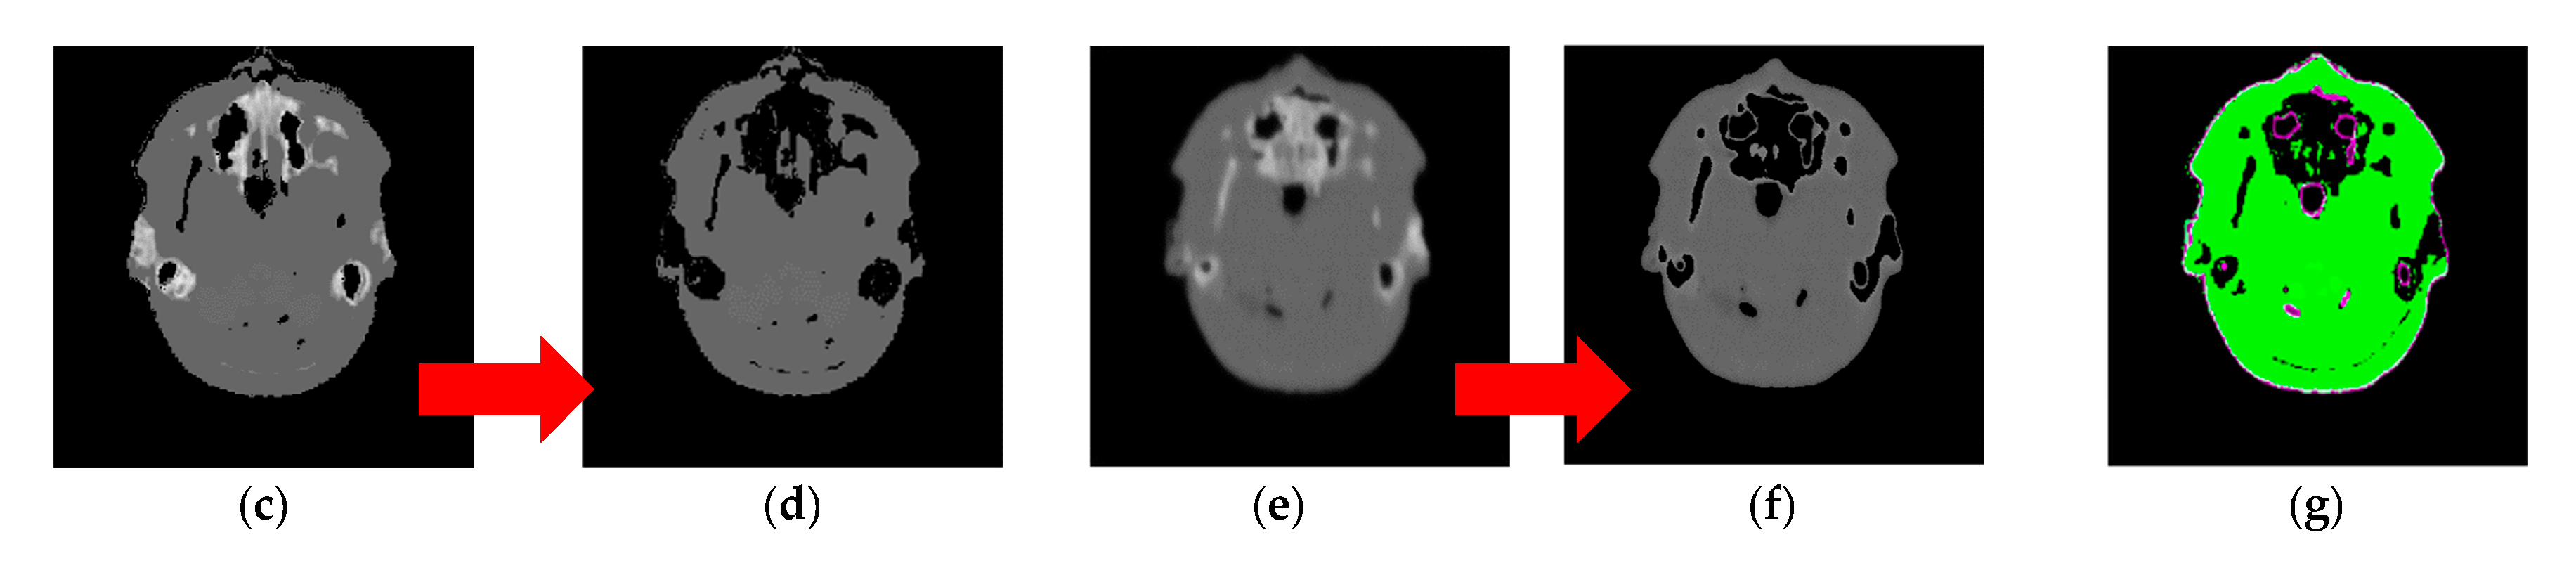

| Segmented result | ![]() Max. iterations = 300 | ![]() Max. iterations = 3600 | ![]() Max. iterations = 3000 | |